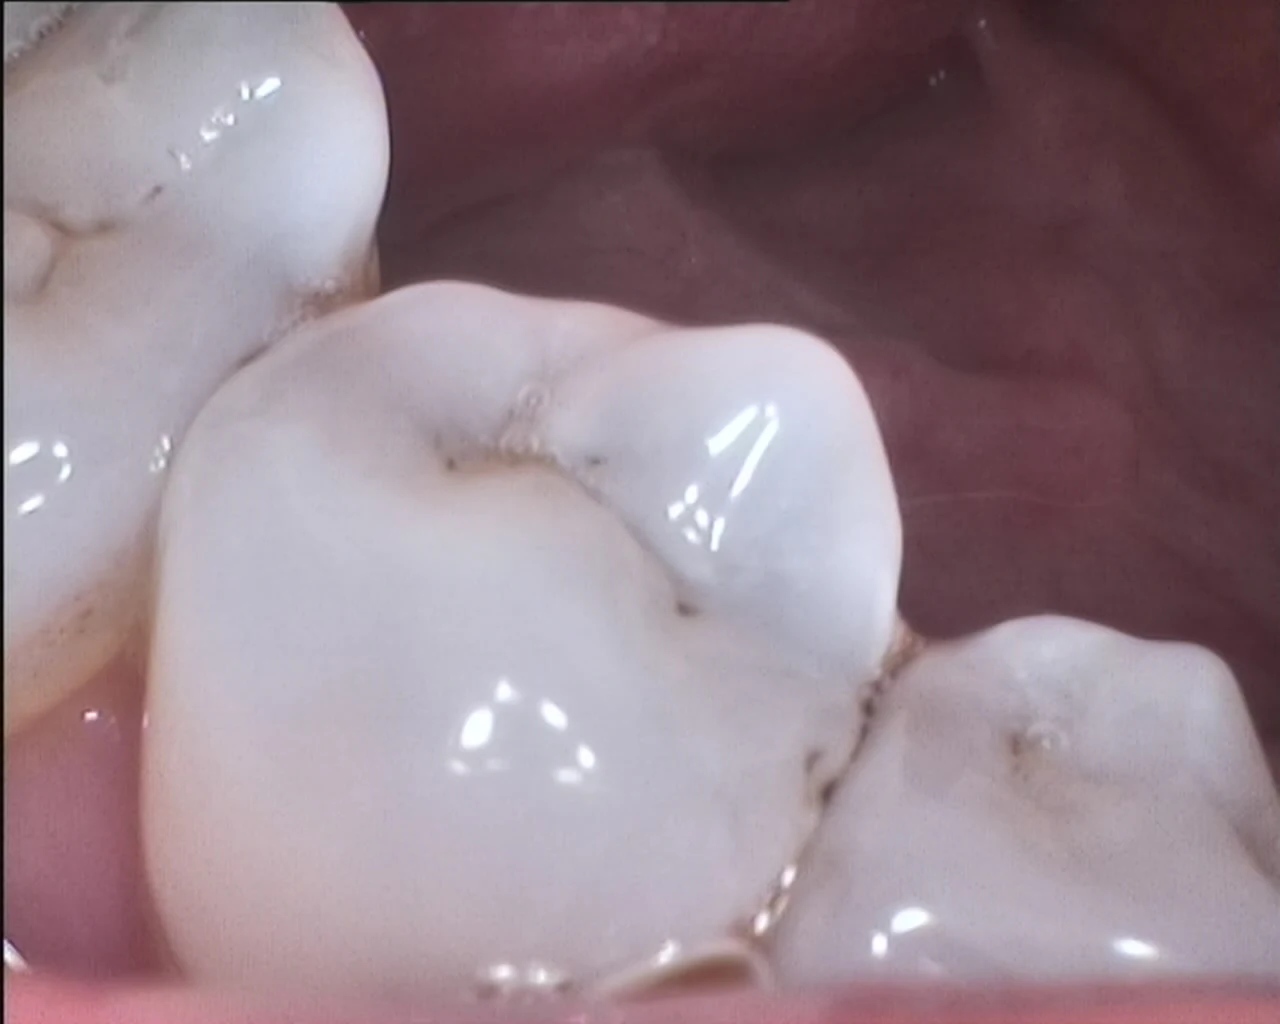

Image sensor1/4 sony CCD

Image resolution: 2.0 mega pixels

Lamp:6pcs white LED( 5600K)

Image sensor: 1/4" Sony CCD

Resolution:5.0 mega pixels`

Lamp:6pcs white LED( 5600K)

Accumulation point:3mm~50mm

Visual Angle:105 degree